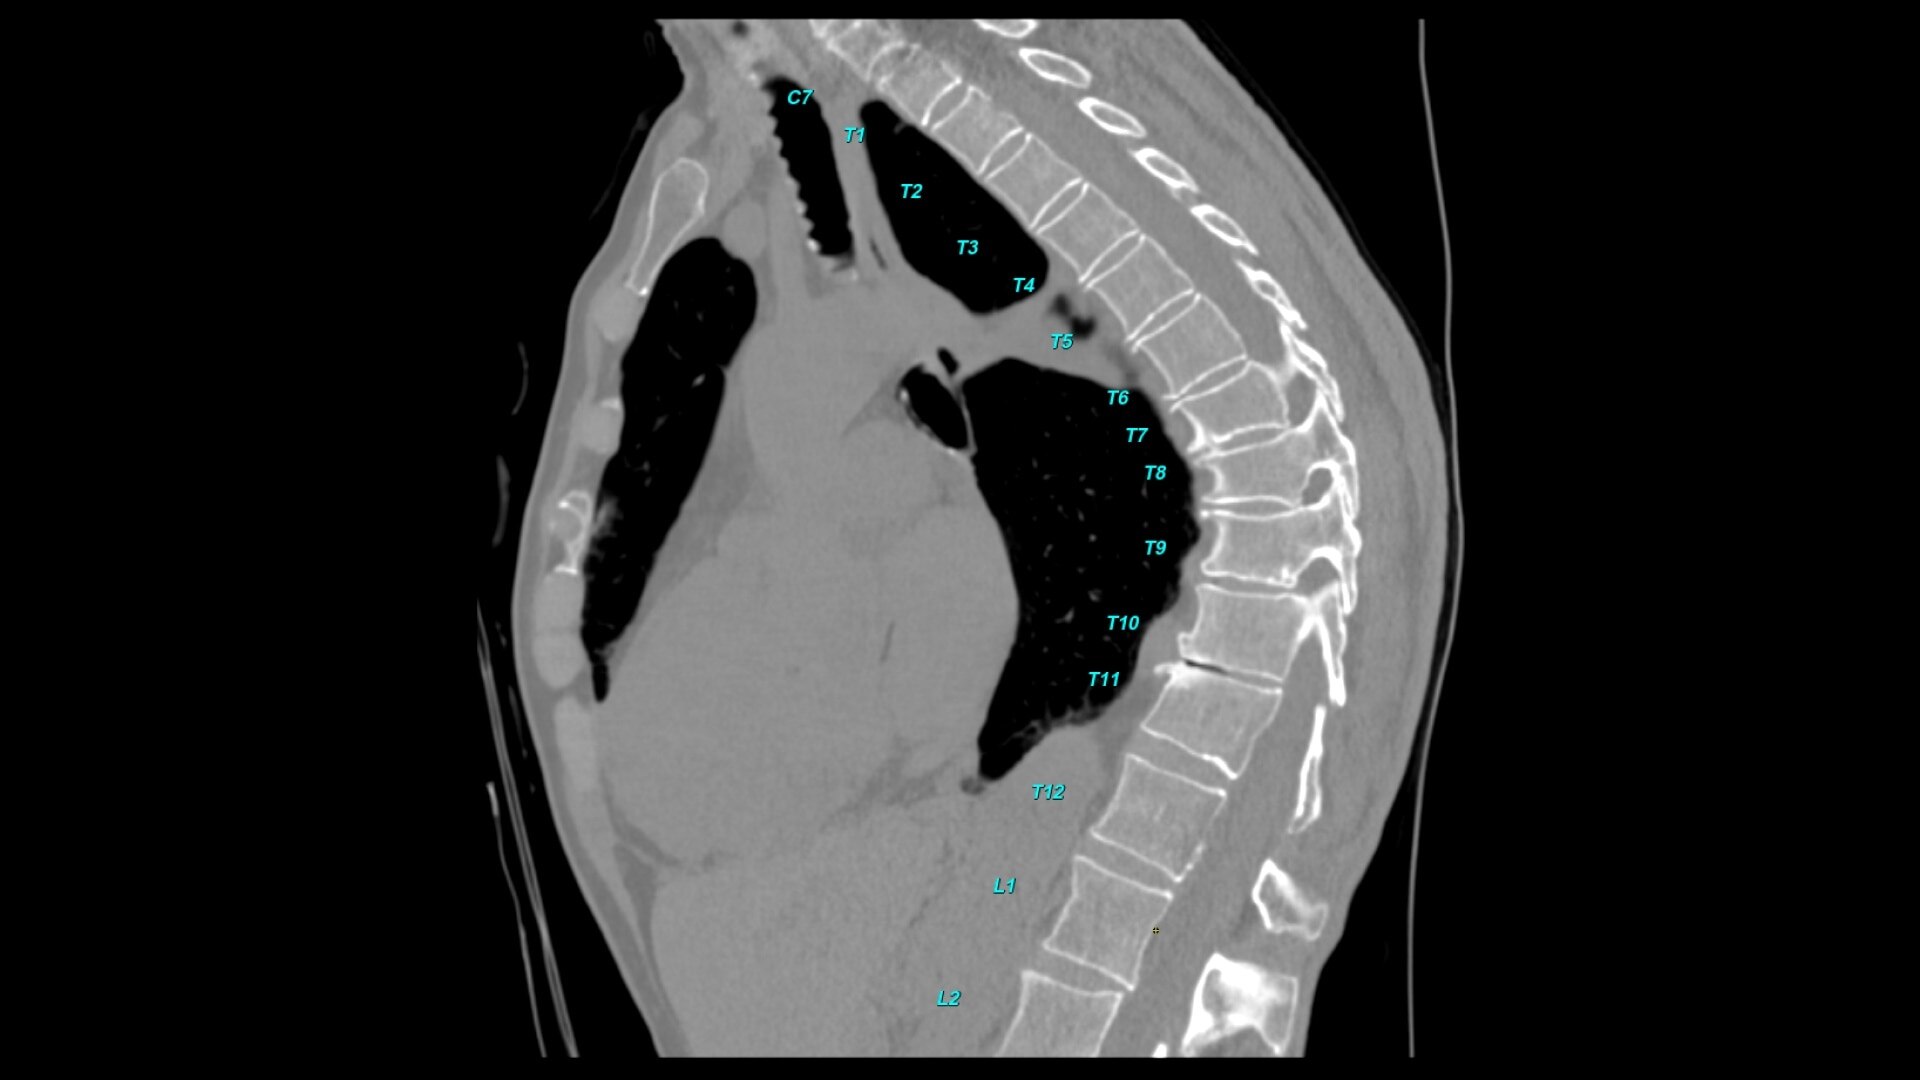

Bone VCAR

Spine assessment with deep-learning based CT application.

• Automated spine labeling

• Automated generation of a 3D trace to generate oblique and straightened reformat views

• Automated generation of oblique views perpendicular to vertebral bodies and disc spaces

• Easily edit the centerline to ensure accurate placement in the most challenging cases

• Accessible for any exam type: trauma, oncology, dedicated spine, general imaging

• Load multiple series and vertebrae labeling will propagate to the different volumes

• Works on full spine acquisitions as well as limited acquisitions containing segments of the spine